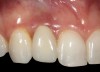

The crown and screw-retained custom abutment were removed, and a surgical cover screw was placed into the implant, thereby allowing spontaneous gingival augmentation in situ (Figure 33 and Figure 34). Note that the lingual aspect of the implant site was significantly more coronal than the labial aspect, which was positive because the defect would be limited to a facial–lingual defect. A fixed RBR bridge was cemented on the adjacent teeth and used as a tooth-supported transitional provisional restoration (Figure 35). A few weeks were allotted to let the soft tissue heal and migrate around the cover screw (Figure 36) to see if there would be complete coverage, thereby allowing a soft-tissue augmentation procedure to be performed with primary flap closure as in clinical scenario No. 2. The major obstacle in achieving a positive tissue response was that the implant depth was also deficient because the implant–abutment connection was at the level of the free gingival margin. It was decided that the best treatment option would be to remove the implant. A high-powered reverse-torque device (Fixture Remover Kit, NeoBiotech, www.neobiotechus.com) was used to remove the implant atraumatically (Figure 38 through Figure 41). The implant socket was allowed to heal for several months not unlike an extracted tooth (Figure 42). A new implant was placed in a better position from both a restorative and esthetic perspective (Figure 43), and after a few months of healing, a new crown was made (Figure 44). A satisfactory functional and esthetic result was achieved (Figure 45 and Figure 46) without employing pink porcelain.

Fig 44. A new metal-alloy abutment was fabricated for the narrow-diameter implant with a cement-retained metal-ceramic crown.

Fig 45. The definitive crown tooth No. 26 seated in place and provisionally cemented. The recession defect was eliminated with the removal and replacement of a new implant in the proper position.

Fig 46. The post-treatment radiograph showing a healthy stable implant and restoration.